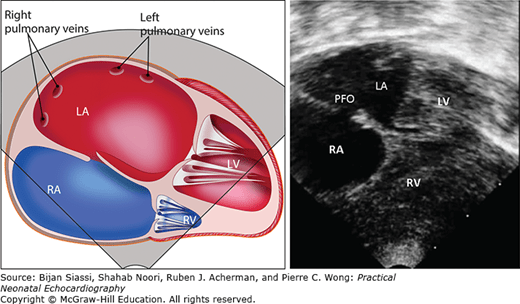

small pfo in newborn sale